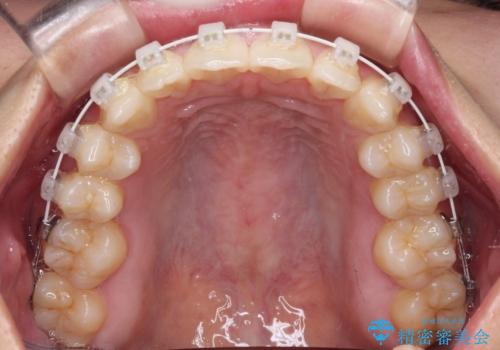

- 矯正装置

- 審美装置

マウスピースでもワイヤーでも対応可能でしたが、自己管理の煩わしさからマウスピース矯正は避けることとしました。

ワイヤー装置により矯正治療を行うとともに舌突出癖改善のためのトレーニングをしっかりと行っていただき、咬み合わせが安定した位置となったタイミングで下顎前歯にブリッジの仮歯を装着していく計画としました。